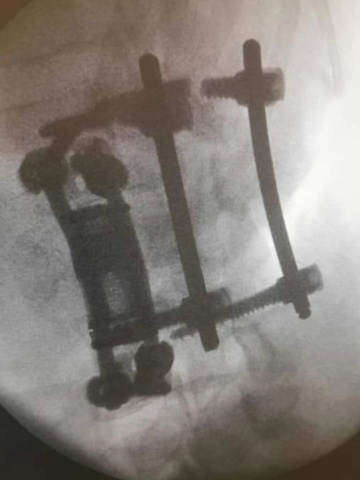

Newman phải cắm một số thanh kim loại vào xương lưng. Ảnh: Mercury Press.

Newman đã thực hiện phẫu thuật và phải gắn những thanh kim loại y tế vào lưng. Tuy nhiên, tổn thương ở dây thần kinh khiến chàng trai sinh năm 1993 mất cảm giác ở chân.